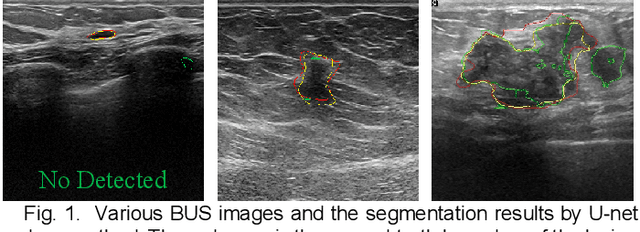

Abstract:The AI-based assisted diagnosis programs have been widely investigated on medical ultrasound images. Complex scenario of ultrasound image, in which the coupled interference of internal and external factors is severe, brings a unique challenge for localize the object region automatically and precisely in ultrasound images. In this study, we seek to propose a more general and robust Benchmark Attention Adaptive Framework (BAAF) to assist doctors segment or diagnose lesions and tissues in ultrasound images more quickly and accurately. Different from existing attention schemes, the BAAF consists of a parallel hybrid attention module (PHAM) and an adaptive calibration mechanism (ACM). Specifically, BAAF first coarsely calibrates the input features from the channel and spatial dimensions, and then adaptively selects more robust lesion or tissue characterizations from the coarse-calibrated feature maps. The design of BAAF further optimizes the "what" and "where" focus and selection problems in CNNs and seeks to improve the segmentation accuracy of lesions or tissues in medical ultrasound images. The method is evaluated on four medical ultrasound segmentation tasks, and the adequate experimental results demonstrate the remarkable performance improvement over existing state-of-the-art methods. In addition, the comparison with existing attention mechanisms also demonstrates the superiority of BAAF. This work provides the possibility for automated medical ultrasound assisted diagnosis and reduces reliance on human accuracy and precision.

Abstract:Breast cancer is one of the common cancers that endanger the health of women globally. Accurate target lesion segmentation is essential for early clinical intervention and postoperative follow-up. Recently, many convolutional neural networks (CNNs) have been proposed to segment breast tumors from ultrasound images. However, the complex ultrasound pattern and the variable tumor shape and size bring challenges to the accurate segmentation of the breast lesion. Motivated by the selective kernel convolution, we introduce an enhanced selective kernel convolution for breast tumor segmentation, which integrates multiple feature map region representations and adaptively recalibrates the weights of these feature map regions from the channel and spatial dimensions. This region recalibration strategy enables the network to focus more on high-contributing region features and mitigate the perturbation of less useful regions. Finally, the enhanced selective kernel convolution is integrated into U-net with deep supervision constraints to adaptively capture the robust representation of breast tumors. Extensive experiments with twelve state-of-the-art deep learning segmentation methods on three public breast ultrasound datasets demonstrate that our method has a more competitive segmentation performance in breast ultrasound images.

Abstract:Various deep learning methods have been proposed to segment breast lesion from ultrasound images. However, similar intensity distributions, variable tumor morphology and blurred boundaries present challenges for breast lesions segmentation, especially for malignant tumors with irregular shapes. Considering the complexity of ultrasound images, we develop an adaptive attention U-net (AAU-net) to segment breast lesions automatically and stably from ultrasound images. Specifically, we introduce a hybrid adaptive attention module, which mainly consists of a channel self-attention block and a spatial self-attention block, to replace the traditional convolution operation. Compared with the conventional convolution operation, the design of the hybrid adaptive attention module can help us capture more features under different receptive fields. Different from existing attention mechanisms, the hybrid adaptive attention module can guide the network to adaptively select more robust representation in channel and space dimensions to cope with more complex breast lesions segmentation. Extensive experiments with several state-of-the-art deep learning segmentation methods on three public breast ultrasound datasets show that our method has better performance on breast lesion segmentation. Furthermore, robustness analysis and external experiments demonstrate that our proposed AAU-net has better generalization performance on the segmentation of breast lesions. Moreover, the hybrid adaptive attention module can be flexibly applied to existing network frameworks.